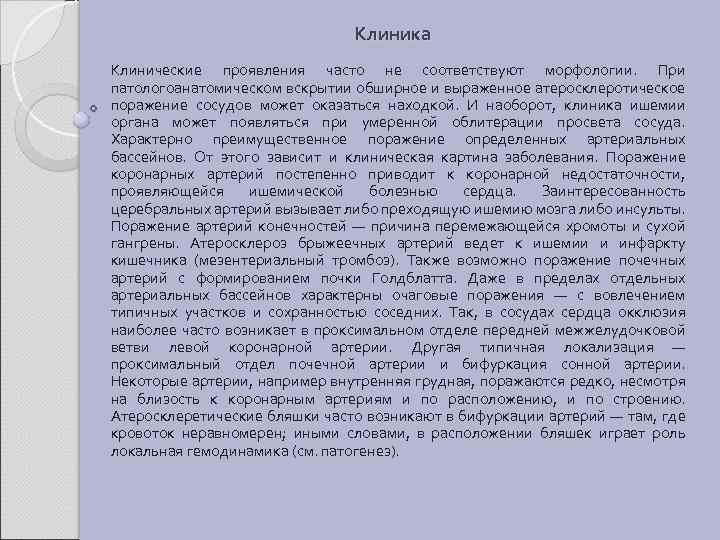

Клиника Клинические проявления часто не соответствуют морфологии. При патологоанатомическом вскрытии обширное и выраженное атеросклеротическое поражение сосудов может оказаться находкой. И наоборот, клиника ишемии органа может появляться при умеренной облитерации просвета сосуда. Характерно преимущественное поражение определенных артериальных бассейнов. От этого зависит и клиническая картина заболевания. Поражение коронарных артерий постепенно приводит к коронарной недостаточности, проявляющейся ишемической болезнью сердца. Заинтересованность церебральных артерий вызывает либо преходящую ишемию мозга либо инсульты. Поражение артерий конечностей — причина перемежающейся хромоты и сухой гангрены. Атеросклероз брыжеечных артерий ведет к ишемии и инфаркту кишечника (мезентериальный тромбоз). Также возможно поражение почечных артерий с формированием почки Голдблатта. Даже в пределах отдельных артериальных бассейнов характерны очаговые поражения — с вовлечением типичных участков и сохранностью соседних. Так, в сосудах сердца окклюзия наиболее часто возникает в проксимальном отделе передней межжелудочковой ветви левой коронарной артерии. Другая типичная локализация — проксимальный отдел почечной артерии и бифуркация сонной артерии. Некоторые артерии, например внутренняя грудная, поражаются редко, несмотря на близость к коронарным артериям и по расположению, и по строению. Атеросклеретические бляшки часто возникают в бифуркации артерий — там, где кровоток неравномерен; иными словами, в расположении бляшек играет роль локальная гемодинамика (см. патогенез).